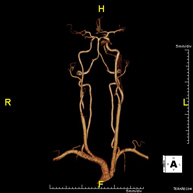

Prueba diagnóstica no invasiva que consiste en el estudio vascular del sector aorto-ilíaco y de los vasos arteriales de ambas extremidades inferiores, obteniendo imágenes de alta definición anatómica mediante el empleo de un campo electromagnético y ondas de radio (con un emisor y un receptor). Es indispensable el uso de contraste paramagnético (Gadolinio). Sin embargo, no utiliza radiación ionizante. La calidad de las imágenes permite realizar reconstrucciones en 2D y 3D. Está especialmente indicado en aquellos pacientes en los que hay sospecha de enfermedad vascular de ambas extremidades, en pacientes con enfermedad vascular de ambas extremidades como el mapa vascular antes del tratamiento (percutáneo o quirúrgico), como el mapa vascular pre-quirúrgico en pacientes con lesiones óseas o musculares que requieran cirugía, etc. - Angio-RM Arterias renales

Prueba diagnóstica no invasiva que consiste en el estudio de la arteria aorta abdominal, obteniendo imágenes de alta definición anatómica mediante el empleo de un campo electromagnético y ondas de radio (con un emisor y un receptor). Es indispensable el uso de contraste intravenoso paramagnético (gadolinio). Sin embargo, no utiliza radiación ionizante. La calidad de las imágenes permite realizar reconstrucciones en 2D y 3D. Está especialmente indicado en aquellos pacientes en los que hay sospecha de enfermedad vascular de ambas extremidades, en pacientes con enfermedad vascular de ambas extremidades como mapa vascular antes del tratamiento (percutáneo o quirúrgico), como mapa vascular pre-quirúrgico en pacientes con lesiones óseas o musculares que requieran cirugía… - Angio-RM Lesión partes blandas